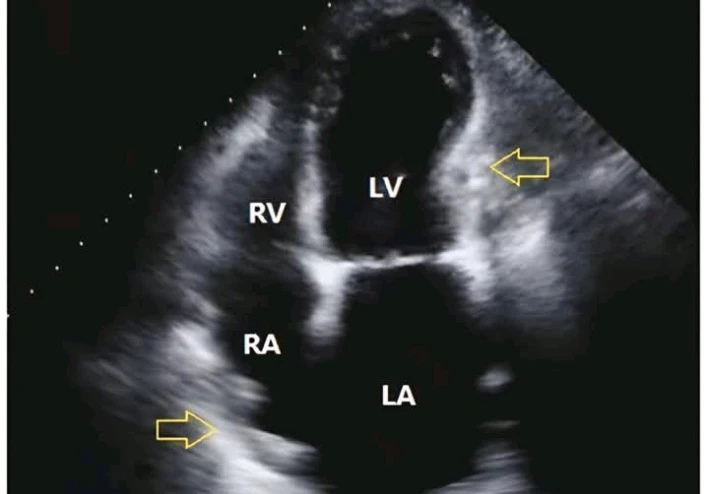

فحصت الولد و عملت له رسم قلب و أيكو

ضربات القلب سريعة شوية لكن كفاءة عضلة القلب ممتازة و صمامات القلب سليمة لكن استوقفتني ملحوظة غريبة جدا ً.

غشاء التامور المحيط بالقلب بيلمع بشكل مش طبيعي و الوريد الأجوف السفلي و الأوردة الكبدية واسعين بشكل غريب.

فحصت الولد و بصيت عليه بالايكو تاني لاقيت الأمور أتحسنت بشكل ملحوظ جدا ً لدرجة إن قلبه فعلا بقى شبه طبيعي.